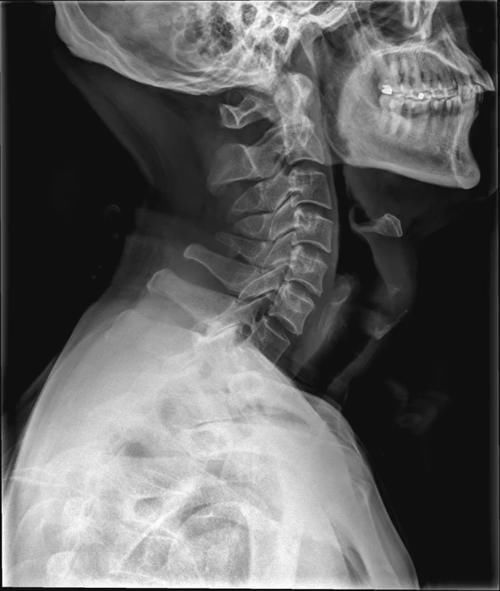

Case3:F,51y;颈2棘突单发性骨软骨瘤。

文章插图

Case4:F,34y;第2、3颈椎棘突骨软骨瘤。